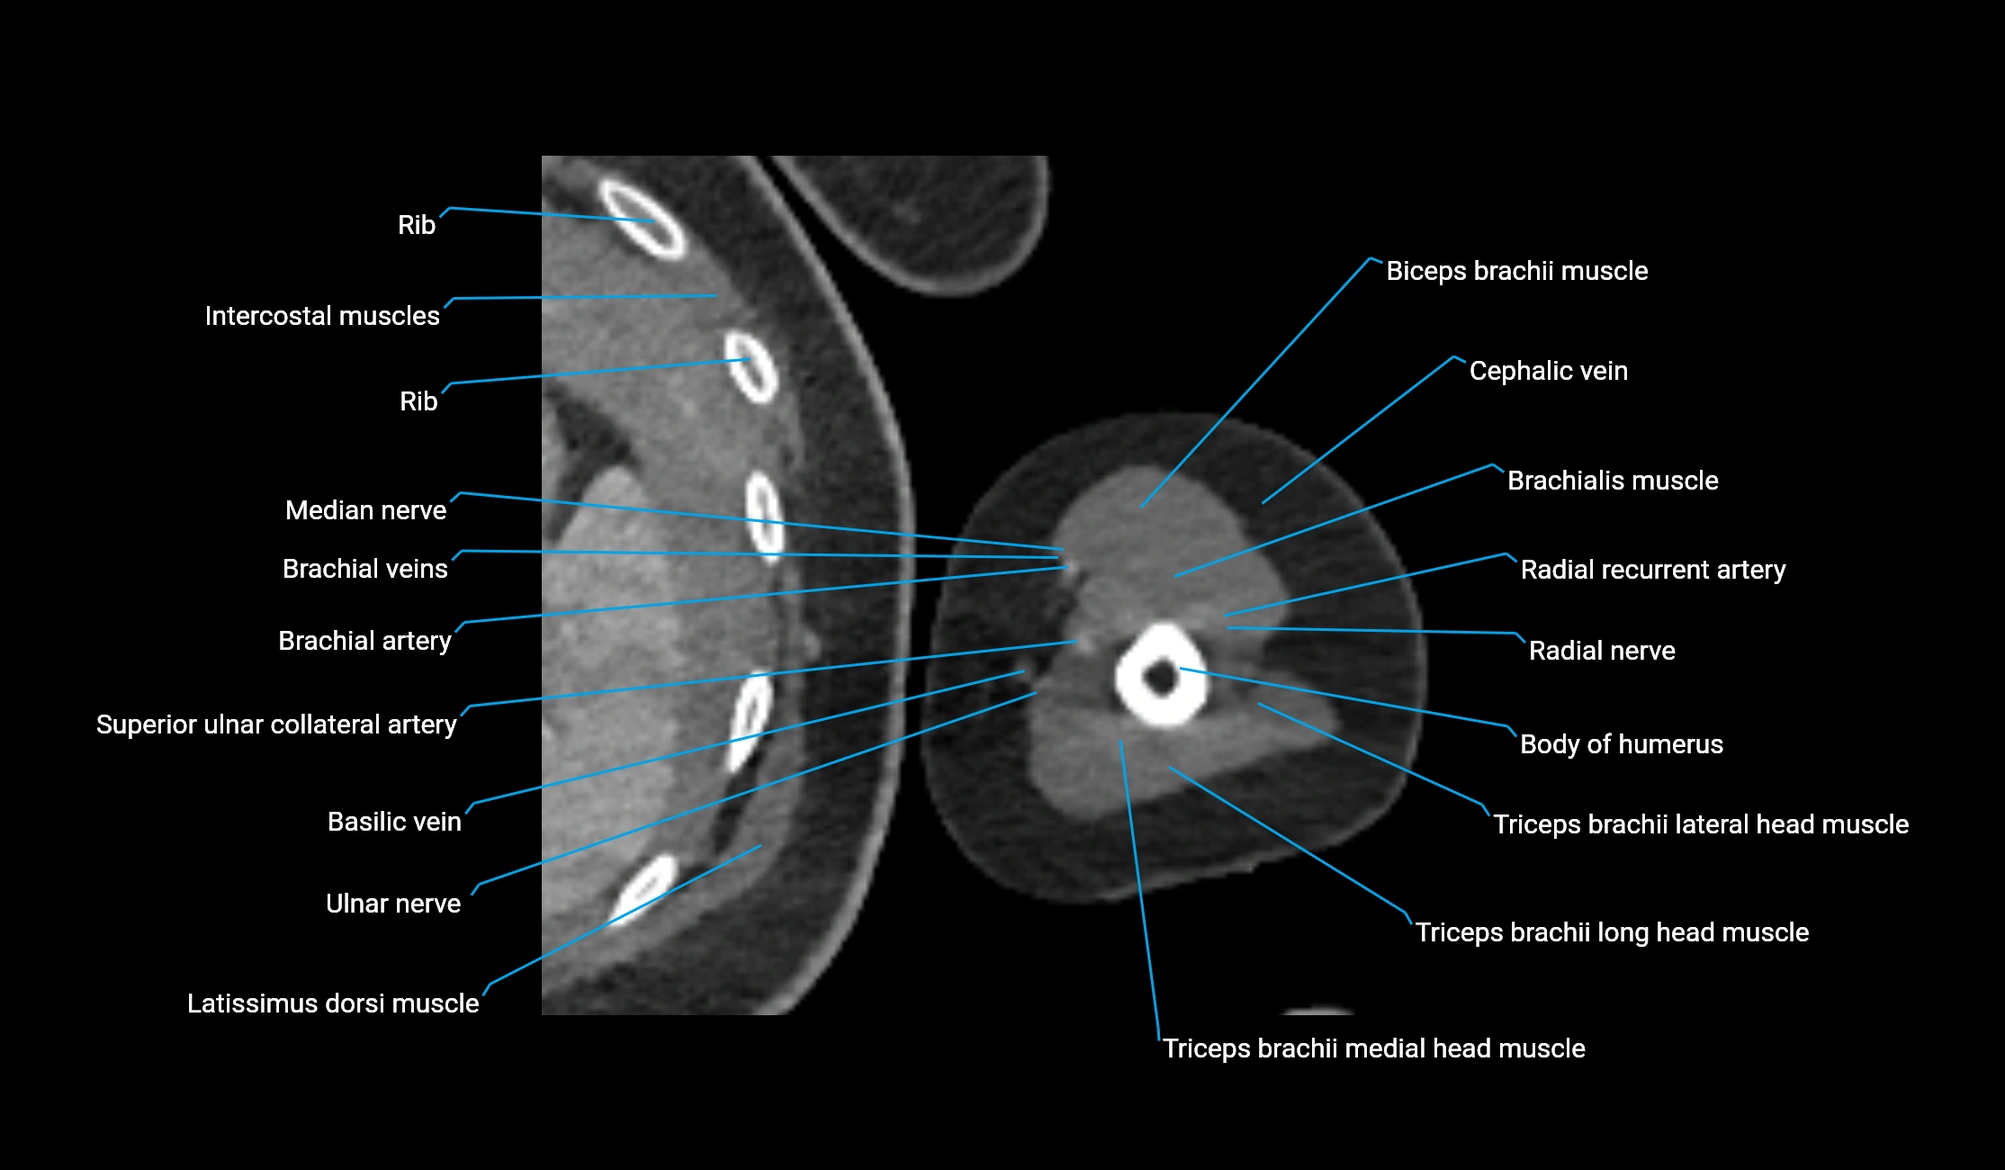

CT image